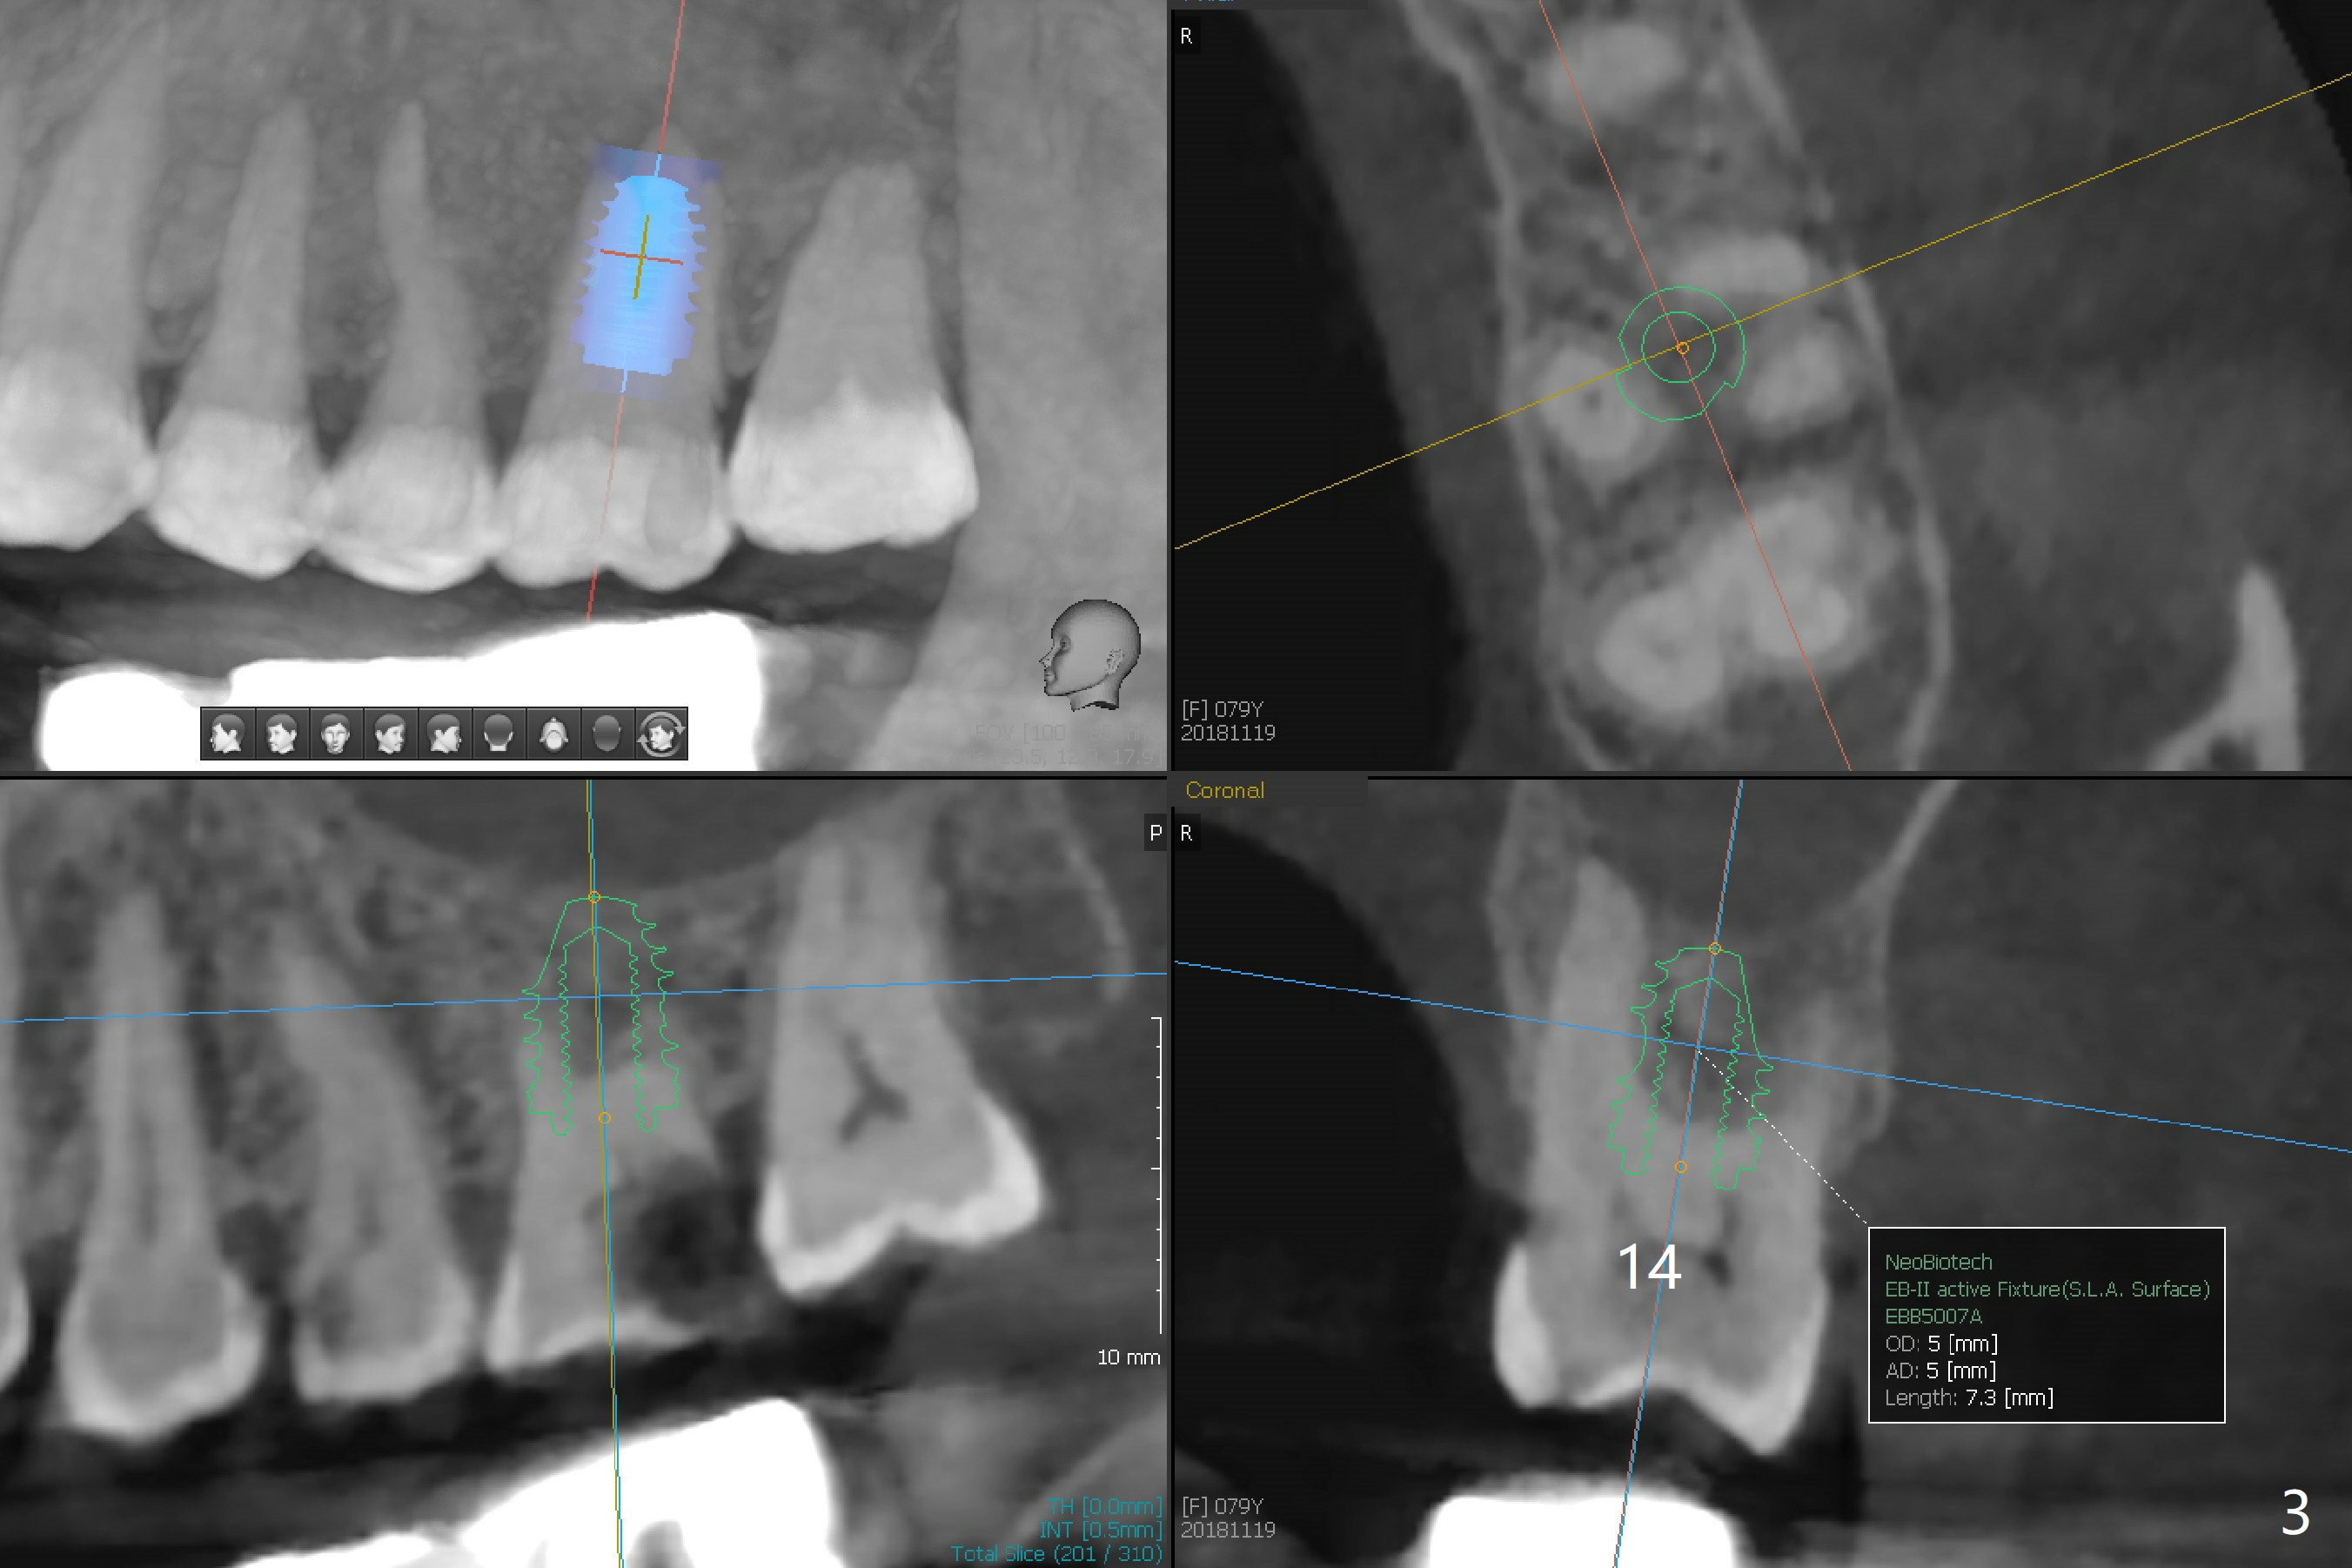

A 79-year-old woman has subgingival symptomatic caries at #14 and residual roots at #4 and 21 (Fig.1). Because of bilateral thick sinus membrane (Fig.2 *) with nasal obstruction, immediate implants at #14 and 4 will be placed without sinus lift (Fig.3,4). To obtain primary stability, a long implant will be placed at #21 (15 or 16 mm), while a narrower implant (3 mm 1-piece, Fig.6)) is safer than 3.8 mm one (2-piece, Fig.5) in term of preventing periimplantitis (buccal thread exposure). Impression has been taken for guide at #14.